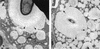

To produce chronic infection, microbial pathogens must escape host immune defenses. Infection with the human pathogenic fungus Cryptococcus neoformans is typically chronic. To understand the mechanism by which C. neoformans survives in tissue after the infection of immunocompetent hosts, we systematically studied the course of pulmonary infection in mice by electron microscopy. The macrophage was the primary phagocytic cell at all times of infection, but neutrophils also ingested yeast. Alveolar macrophages rapidly internalized yeast cells after intratracheal infection, and intracellular yeast cells were noted at all times of infection from 2 h through 28 days. However, the proportion of yeast cells in the intracellular and extracellular spaces varied with the time of infection. Early in infection, yeast cells were found predominantly in the intracellular compartment. A shift toward extracellular predominance occurred by 24 h that was accompanied by macrophage cytotoxicity and disruption. Later in infection, intracellular persistence in vivo was associated with replication, residence in a membrane-bound phagosome, polysaccharide accumulation inside cells, and cytotoxicity to macrophages, despite phagolysosomal fusion. Many phagocytic vacuoles with intracellular yeast had discontinuous membranes. Macrophage infection resulted in cells with a distinctive appearance characterized by large numbers of vacuoles filled with polysaccharide antigen. Similar results were observed in vitro using a macrophage-like cell line. Our results show that C. neoformans is a facultative intracellular pathogen in vivo. Furthermore, our observations suggest that C. neoformans occupies a unique niche among the intracellular pathogens whereby survival in phagocytic cells is accompanied by intracellular polysaccharide production.